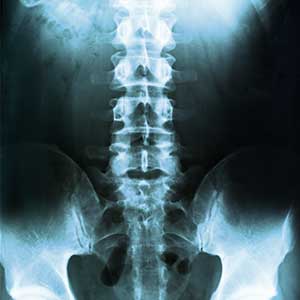

X-rays

Provide images of bones in the spine to identify fractures, degenerative changes, or abnormalities.